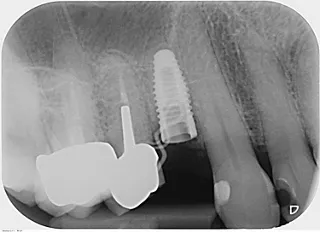

Beim Follow-up nach 6 Monaten wurde eine digitale Volumentomographie (DVT) erstellt und eine periapikale Röntgenaufnahme angefertigt. Diese bestätigten ein adäquates Knochenvolumen sowie eine adäquate Knochendichte und dreidimensionale Positionierung des Implantats (Abb. 13-15).

Die intraoralen Aufnahmen und die Röntgenaufnahme, die beim Follow-up zwei Jahre nach dem Setzen des Straumann® BLX Roxolid® SLActive® Implantats und dem simultanen Knochenaugmentationsverfahren angefertigt wurden, bestätigen den Erfolg der Behandlung (Abb. 21-23).